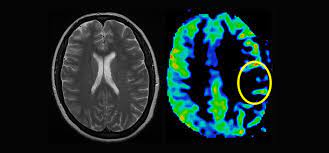

A non-invasive imaging procedure called as perfusion imaging reveals how blood flows through tissues and organs. Perfusion imaging techniques efficiently produce both perfusion measurements and perfusion maps of the area of specific interest. It aids in identifying nutritive blood supply to a crucial component of tissue. The use of these imaging modalities in the perfusion imaging market has increased over time. There are several different perfusion imaging tools on the market. These instruments include computed tomography and microspheres. These imaging technologies help to map the blood flow across the vascular network of the brain.